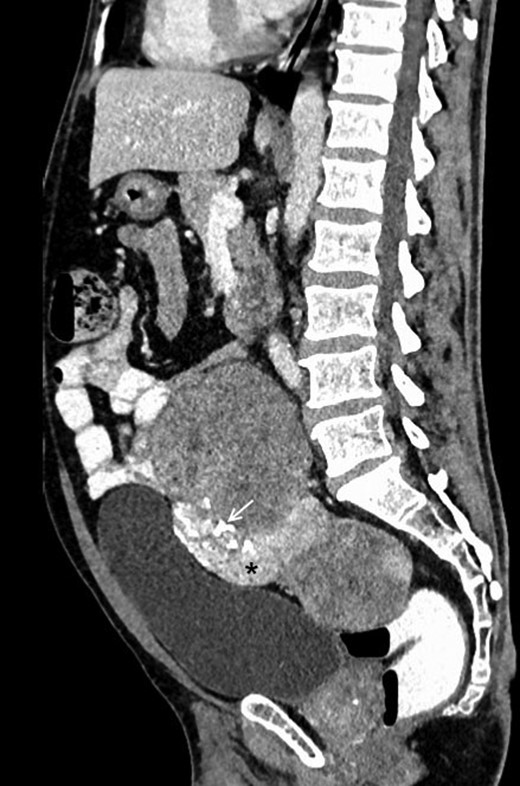

A 48-year-male patient presented with awareness of gradually increasing lower abdominal lump and abdominal discomfort for 8 months. There was no history of anorexia and weight loss. He was a non-smoker and non-alcoholic. His general physical examination was unremarkable with no clinical evidence of hepatic disease and adrenal or pituitary insufficiency. On abdominal examination, about 8 × 10 cm non-tender, hard, well-defined intra-abdominal lump was present in hypogastrium, which was extending into right iliac fossa, right lumbar and umbilical region for which the lower margin was not palpable. The lump was bimanually palpable on rectal examination. It was causing intra-luminal projection within rectum without any mucosal irregularity. His initial basic laboratory investigations which included hemogram, coagulogram, blood sugar, serum sodium, potassium, chloride, calcium, renal and liver function tests and urine analysis were within normal range. CECT abdomen (Figs 1 and 2) revealed a 20 × 15 × 7 cm heterogenous well-defined lobulated mass with calcification and areas of necrosis in the pre-sacral region and was extending superiorly up to the lower border of L3. It was indenting into the bladder anteriorly and rectum posteriorly, also abutting pelvic vessels but maintaining fat planes with all these structures. This mass was causing bilateral hydroureteronephrosis.

Contrast-enhanced sagittal reformatted CT section of the abdomen depicts a large enhancing mass posterior to the urinary bladder and anterior to the lower lumbar vertebrae and sacrum. The lesion is heterogeneously enhancing with a small hyperenhancing component (asterisk). Foci of calcification are noted within the lesion (white arrow). Note that the fat planes with the bowel and the urinary bladder are maintained.